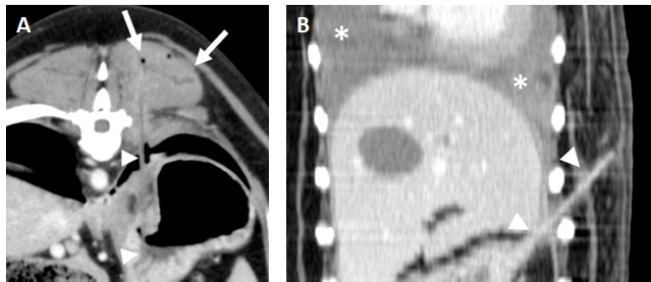

Fig. 3. Examples of gastric foreign bodies from the stomach with the ending tip in the paravertebral or thoracic wall soft tissues. A. Transverse post-contrast CT image (level 40 HU, width 250 HU) of a dog with a wooden skewer (arrowheads) extending from the stomach and ending in the left epaxial muscles. Mild fluid accumulation and emphysema are seen surrounding the ending tip of the foreign body (arrows). B. Dorsal post-contrast CT image (level 40 HU, width 250 HU) of a dog with a wooden skewer (arrowheads) perforating the gastric wall with an oblique orientation ending in the subcutaneous tissue of the left thoracic wall. A moderate bilateral pleural effusion is seen associated with this foreign body (asterisks).

Another recurrent finding was seen when the ending tip of the wooden skewer was located within the paraspinal or costal soft tissues and consisted of intramuscular and subcutaneous fluid- and gas-filled lesions with an irregular and markedly enhancing wall, confirmed as abscesses (Fig. 3). In spite of being a frequent feature with penetrating foreign bodies that migrate from the lungs (Jacques et al., 2019; Griffeuille et al., 2021; Hennessey et al., 2022), this type of lesions in the paraspinal muscles are uncommon with penetrating wooden skewers from the gastrointestinal tract based in the previously published literature. Additional subcutaneous fat stranding and emphysema were also frequent; however, no bony lesions were detected.